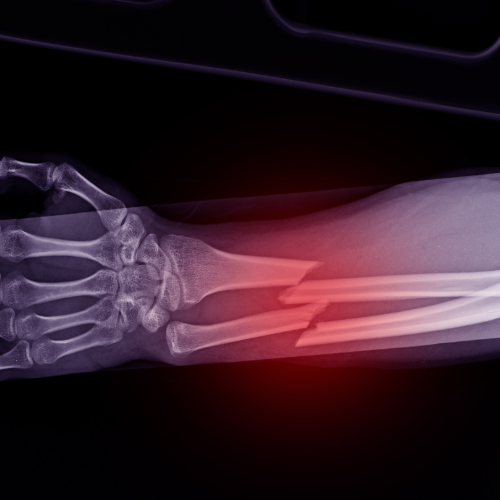

Traumatismos Do Antebraço

Lesões causadas por quedas, impactos ou acidentes, que podem afetar ossos, músculos e nervos. Podem incluir fraturas e luxações, exigindo avaliação ortopédica precisa e tratamento adequado para evitar sequelas.

Fraturas Do Rádio Distal

Muito comuns em quedas sobre o braço estendido, essas fraturas afetam o osso do antebraço próximo ao punho. Causam dor, inchaço e limitação de movimento, podendo exigir imobilização ou cirurgia, conforme a gravidade.